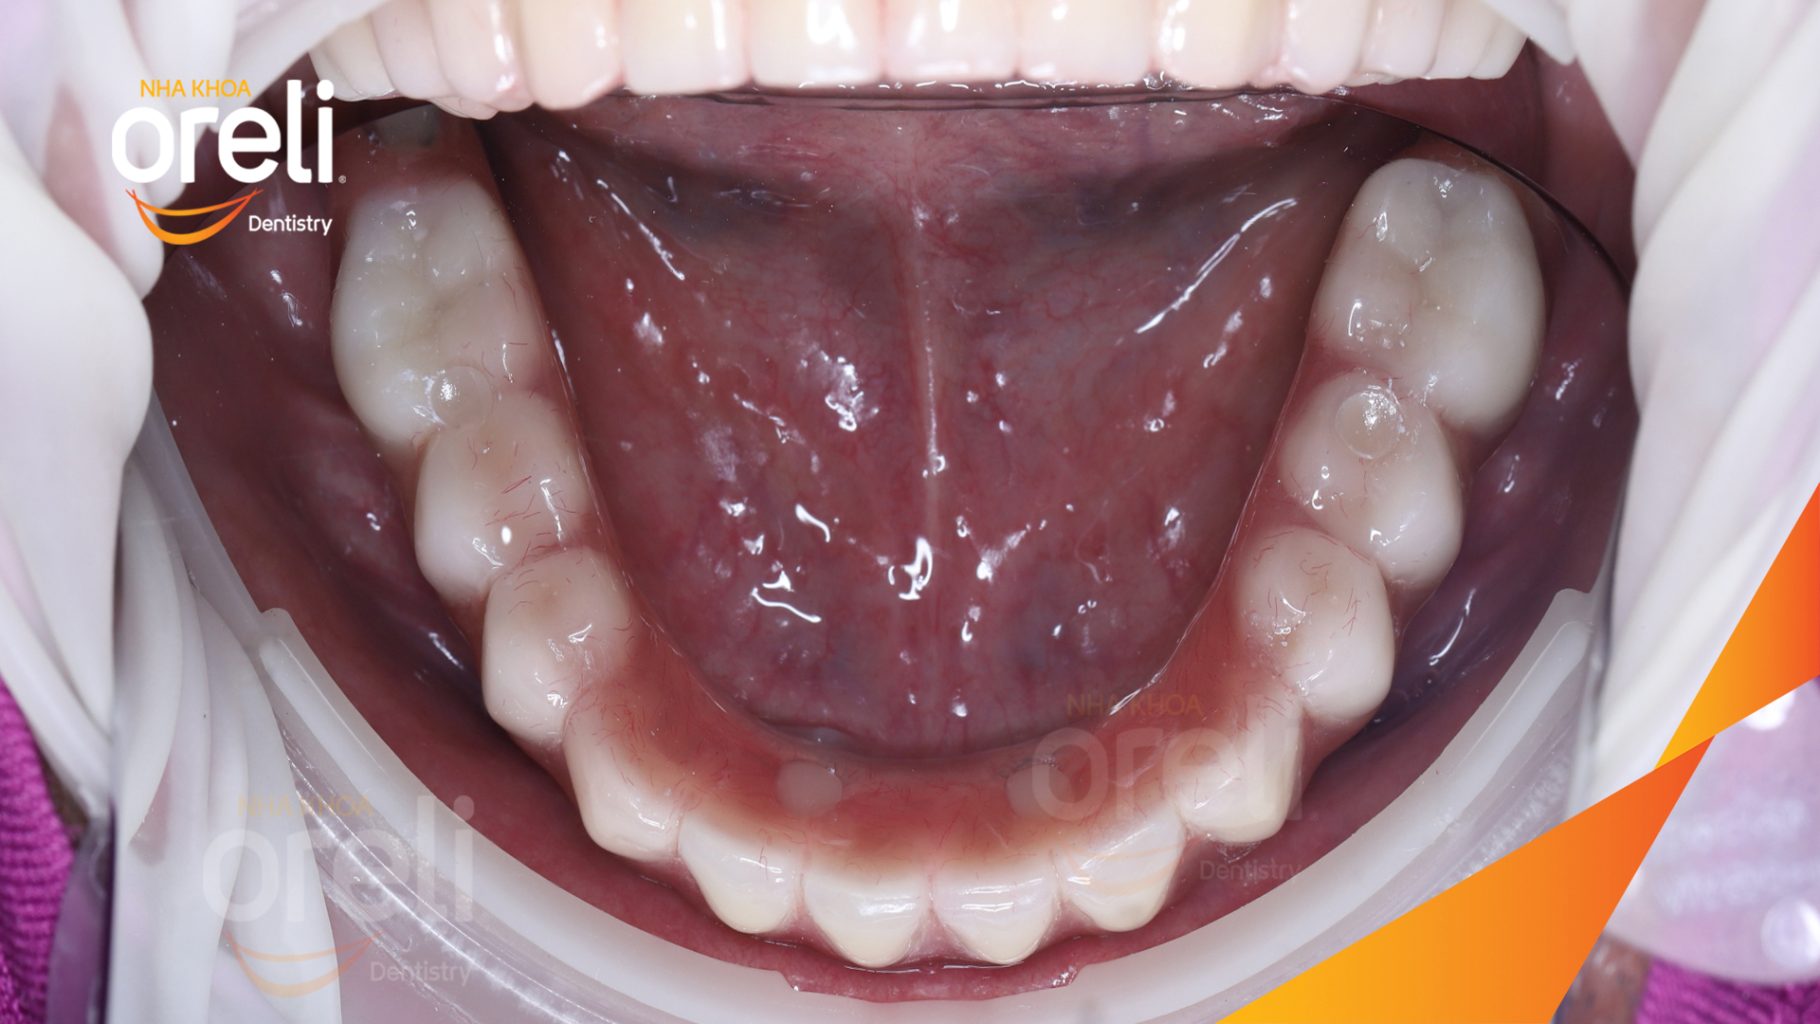

Tình trạng: Mất răng toàn bộ hàm trên và hàm dưới

Giải pháp: Trồng răng implant hai hàm với phục hình tạm

Kết quả: Ăn nhai trở lại và nụ cười thẩm mỹ

Hình ảnh thực tế